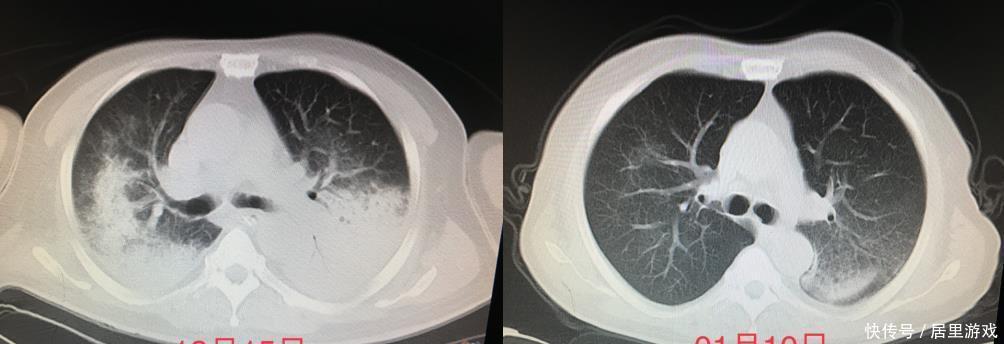

文章插图

(患者肺部影像学动态变化情况)

经过连续两天的俯卧位通气、多器官功能支持治疗后,患者氧合得到充分改善,呼吸机参数逐渐下调。

为避免呼吸机相关肺炎的发生,呼吸与危重症医学科与ICU组成的联合救治团队在气管插管的第7天为患者拔除了气管插管,改用经鼻湿化高流量氧疗。